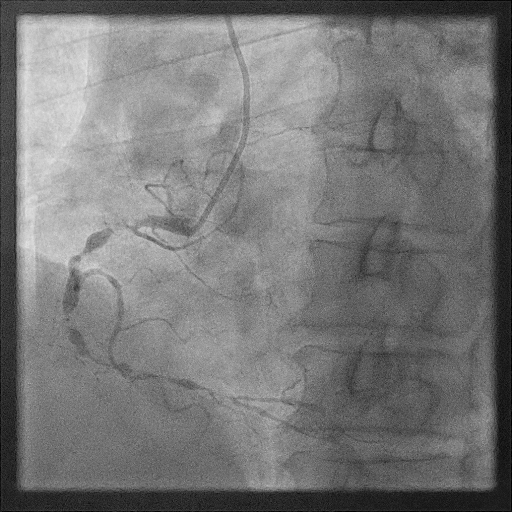

我院右冠基础造影

RCA:全程弥漫多处95%以上狭窄伴重度钙化,最重处次全闭塞,血流TIMI2级。